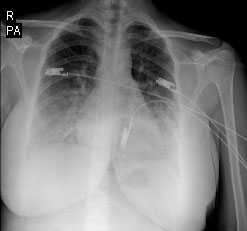

The 21-year-old woman was admitted to the department of obstetrics and gynecology at the gestational age of 37 weeks with bleeding. There was no feature in her medical history. She was a housewife, gravida 1, parity 0. Her pregnancy was terminated by cesarean section due to placenta ablation and intrauterine ex-fetus. Erythrocyte suspension was transfused for intraoperative bleeding and low postoperative hemoglobin value. An anaphylactic reaction developed in the patient during blood transfusion (after about 100 ml). Deep hypotension, bilateral diffuse bronchospasm and anasarca edema were observed to the patient. Adrenaline (1:10000) was administered intravenously to the patient andinvasive blood pressure monitoring was performed. She was taken to the intensive care unit. The Glaskow coma score (GCS) was 14, physical examination was normal and she had not hypotension and tachycardia. Laboratory findings were hemoglobin: 7,4 g/dl, hematocrit: 23%, platelet: 75000, creatinine: 1,19 mg/dl, lactate dehydrogenase (LDH): 508 U/L, calcium: 6,6 mg/dl.  The Following hemoglobin was 5,5 g/dl thus 3 units of washed erythrocyte suspension were transfused to the patient. The patient complained of dyspnea, orthopnea, and lower limb edema after 3 hours from the blood transfusion. Oxygen saturation was 84% in room air. On auscultation, bilateral inspiratory rales were heard at all zones of the lungs and she had bilateral marked pretibial edema. Four liters/minute of nasal oxygen, diuretic (furosemide intravenous) and anticoagulant (enoxaparin 6000 unit 2x1 subcutaneously) were given with predicted pulmonary edema and pulmonary thromboembolism. D-dimer (2.56 μg/ml), troponin-T (123 pg/ml) and LDH (505 U/L) were high. Her arterial blood gas analysis showed pH: 7,52; pO2: 69,6 mmHg; pCO2: 36,2 mmHg; HCO3: 29,2 mmol/L; SO2: 86%. Bilateral infiltrations especially at the middle and lower zones and cardiomegaly were notable on the chest x-ray (Figure 1). The bedside transthoracic echocardiography showed normal right ventricles, pulmonary artery pressure of 30 mmHg, left ventricular EF of 40% by Teicholz and Simpson’s methods (Figure 2). The case was diagnosed with PPCM and she was given treatment consisting of an angiotensin-converting enzyme inhibitor and furosemide. Regression was observed on control chest X-ray (Figure 3). Control levels of D-dimer (2,21 μg/ml), troponin-T (81 pg/ml) and LDH (450 U/L) decreased. When the clinical state findings improved, she was transferred to Department of Obstetrics and Gynecology. The patient was discharged after 5 days.

Figure 3 The control chest x-ray. A control chest x-ray shows bilateral regression of infiltrations.